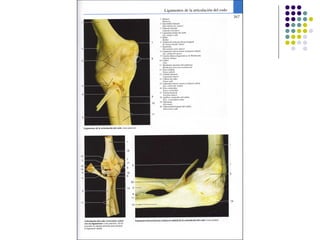

La extremidad superior humana incluye el hombro, el brazo, el codo, la muñeca y la mano. Está diseñada para una variedad de funciones motoras finas como agarrar objetos y realizar tareas manuales complejas. La coordinación precisa de los músculos y los huesos de la extremidad superior es clave para su versatilidad funcional.